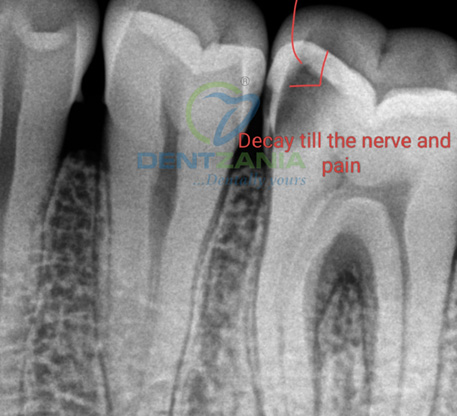

A toothache often needs some sort of treatment by your dentist. The treatment will depend on the underlying cause . However , for a disturbing pain originating from the tooth due to decay or excessive loss of enamel , a root canal treatment provides immediate relief and is the preferred treatment option when the tooth is salvageable !

A root canal is a dental procedure that saves a damaged or infected tooth by replacing the tooth's pulp with a filling and is the most common treatment for a tooth ache that is severe and caused by nerve irritation . It's also known as endodontic treatment. Rootcanals almost instantly relieve a long standing or severe toothache that is caused due to nerve irritation or infection . There is a mystique surrounding Root Canal Treatments, and the reality is that they are not half as bad as people think.

- Decay has reached the tooth pulp (the living tissue inside the tooth).

- Infection or abscesses have developed at the root tip or inside the tooth.

- Severe toothache.

- Swelling and/or tenderness.